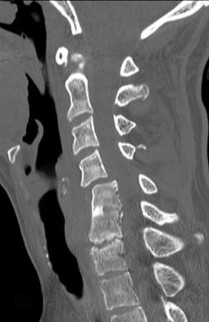

A 45-year-old male with a 20-year history of ankylosing spondylitis presents to the emergency department after a low-energy trip and fall at home. He complains of new-onset, severe lower cervical neck pain. Neurologic examination is unremarkable.

Standard AP, lateral, and odontoid plain radiographs are interpreted as normal. What is the most appropriate next step in management?

Explanation

A 65-year-old male with a known history of ankylosing spondylitis presents to the emergency department after a low-speed motor vehicle collision. A CT scan demonstrates a fracture through the C6-C7 disc space extending into the posterior elements.

What is the most appropriate surgical treatment?

A 62-year-old male with a 20-year history of ankylosing spondylitis presents to the emergency department complaining of new-onset, severe neck pain after a minor fall from a chair. He has no neurologic deficits. Plain radiographs of the cervical spine demonstrate extensive syndesmophytes but no obvious fracture. What is the most appropriate next step in management?